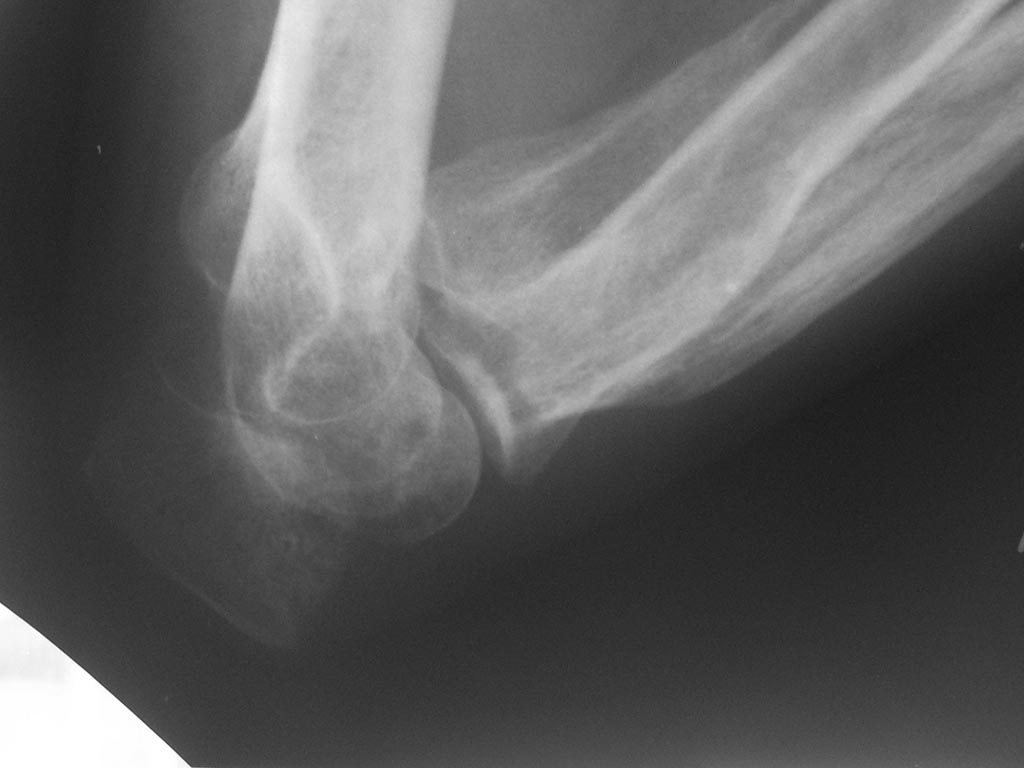

Лечения не было. Сейчас - контрактура и резко выраженный болевой

синдром, в т.ч. вследствие давления trohlea humeri изнутри на кожу. МРТ

или КТ невыполнимо. Тактика?

Вложение не в текстовом формате было извлечено…

Имя     : IMG_0321.JPG

Тип     : image/jpeg

Размер  : 62873 байтов

Url     : http://weborto.net:8080/pipermail/ortho/attachments/20141120/eb188f24/attachment-0005.jpeg